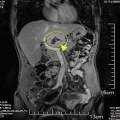

| 影像学检查:(点击查看大图) | 影像检查:上腹增强 CT 检查提示:“右上腹占位”。 |